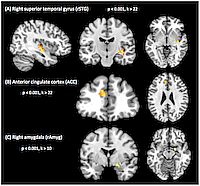

- mittels fMRT-Untersuchungen nachgewiesen, dass Infraschall störend auf Grundfunktionen des menschlichen Gehirns einwirkt.